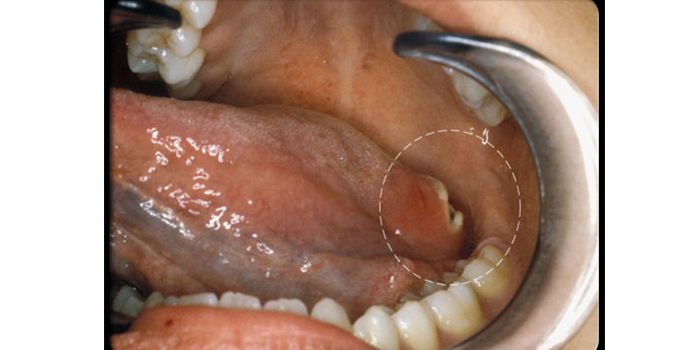

Si kecil saat ini lagi sariawandia jadi susah minum asi ataupun botol karena di balikbibir serta lidahnya ada sariawan. Apalagi jika yang mengalaminya adalah balita berusia 1 tahun. Sariawan terjadi pada bagian dalam bibir gusi hingga rahang.

Untuk mengobatinya anda cukup dengan cara meningkatkan sistem kekebalan tubuhnya yang bisa dilakukan dengan memberikan obat yang terbuat dari ramuan tanaman herbal. Dikemas dalam kemasan tube produk yang merupakan tipe steroid ini praktis dibawa ke mana saja. Bintik kecil dengan warna merah atau keputihan ini akan terasa sangat sakit dan terlebih saat untuk makan.

Obat sariawan untuk anak 1 tahun yang aman cara mengatasi penyakit sariawan yang diderita oleh anak umur 1 tahun sebenarnya tidak begitu sulit. Diketahui bahwa sariawan adalah gangguan kesehatan mulut yang dapat terjadi pada siapa saja tanpa mengenal usia.